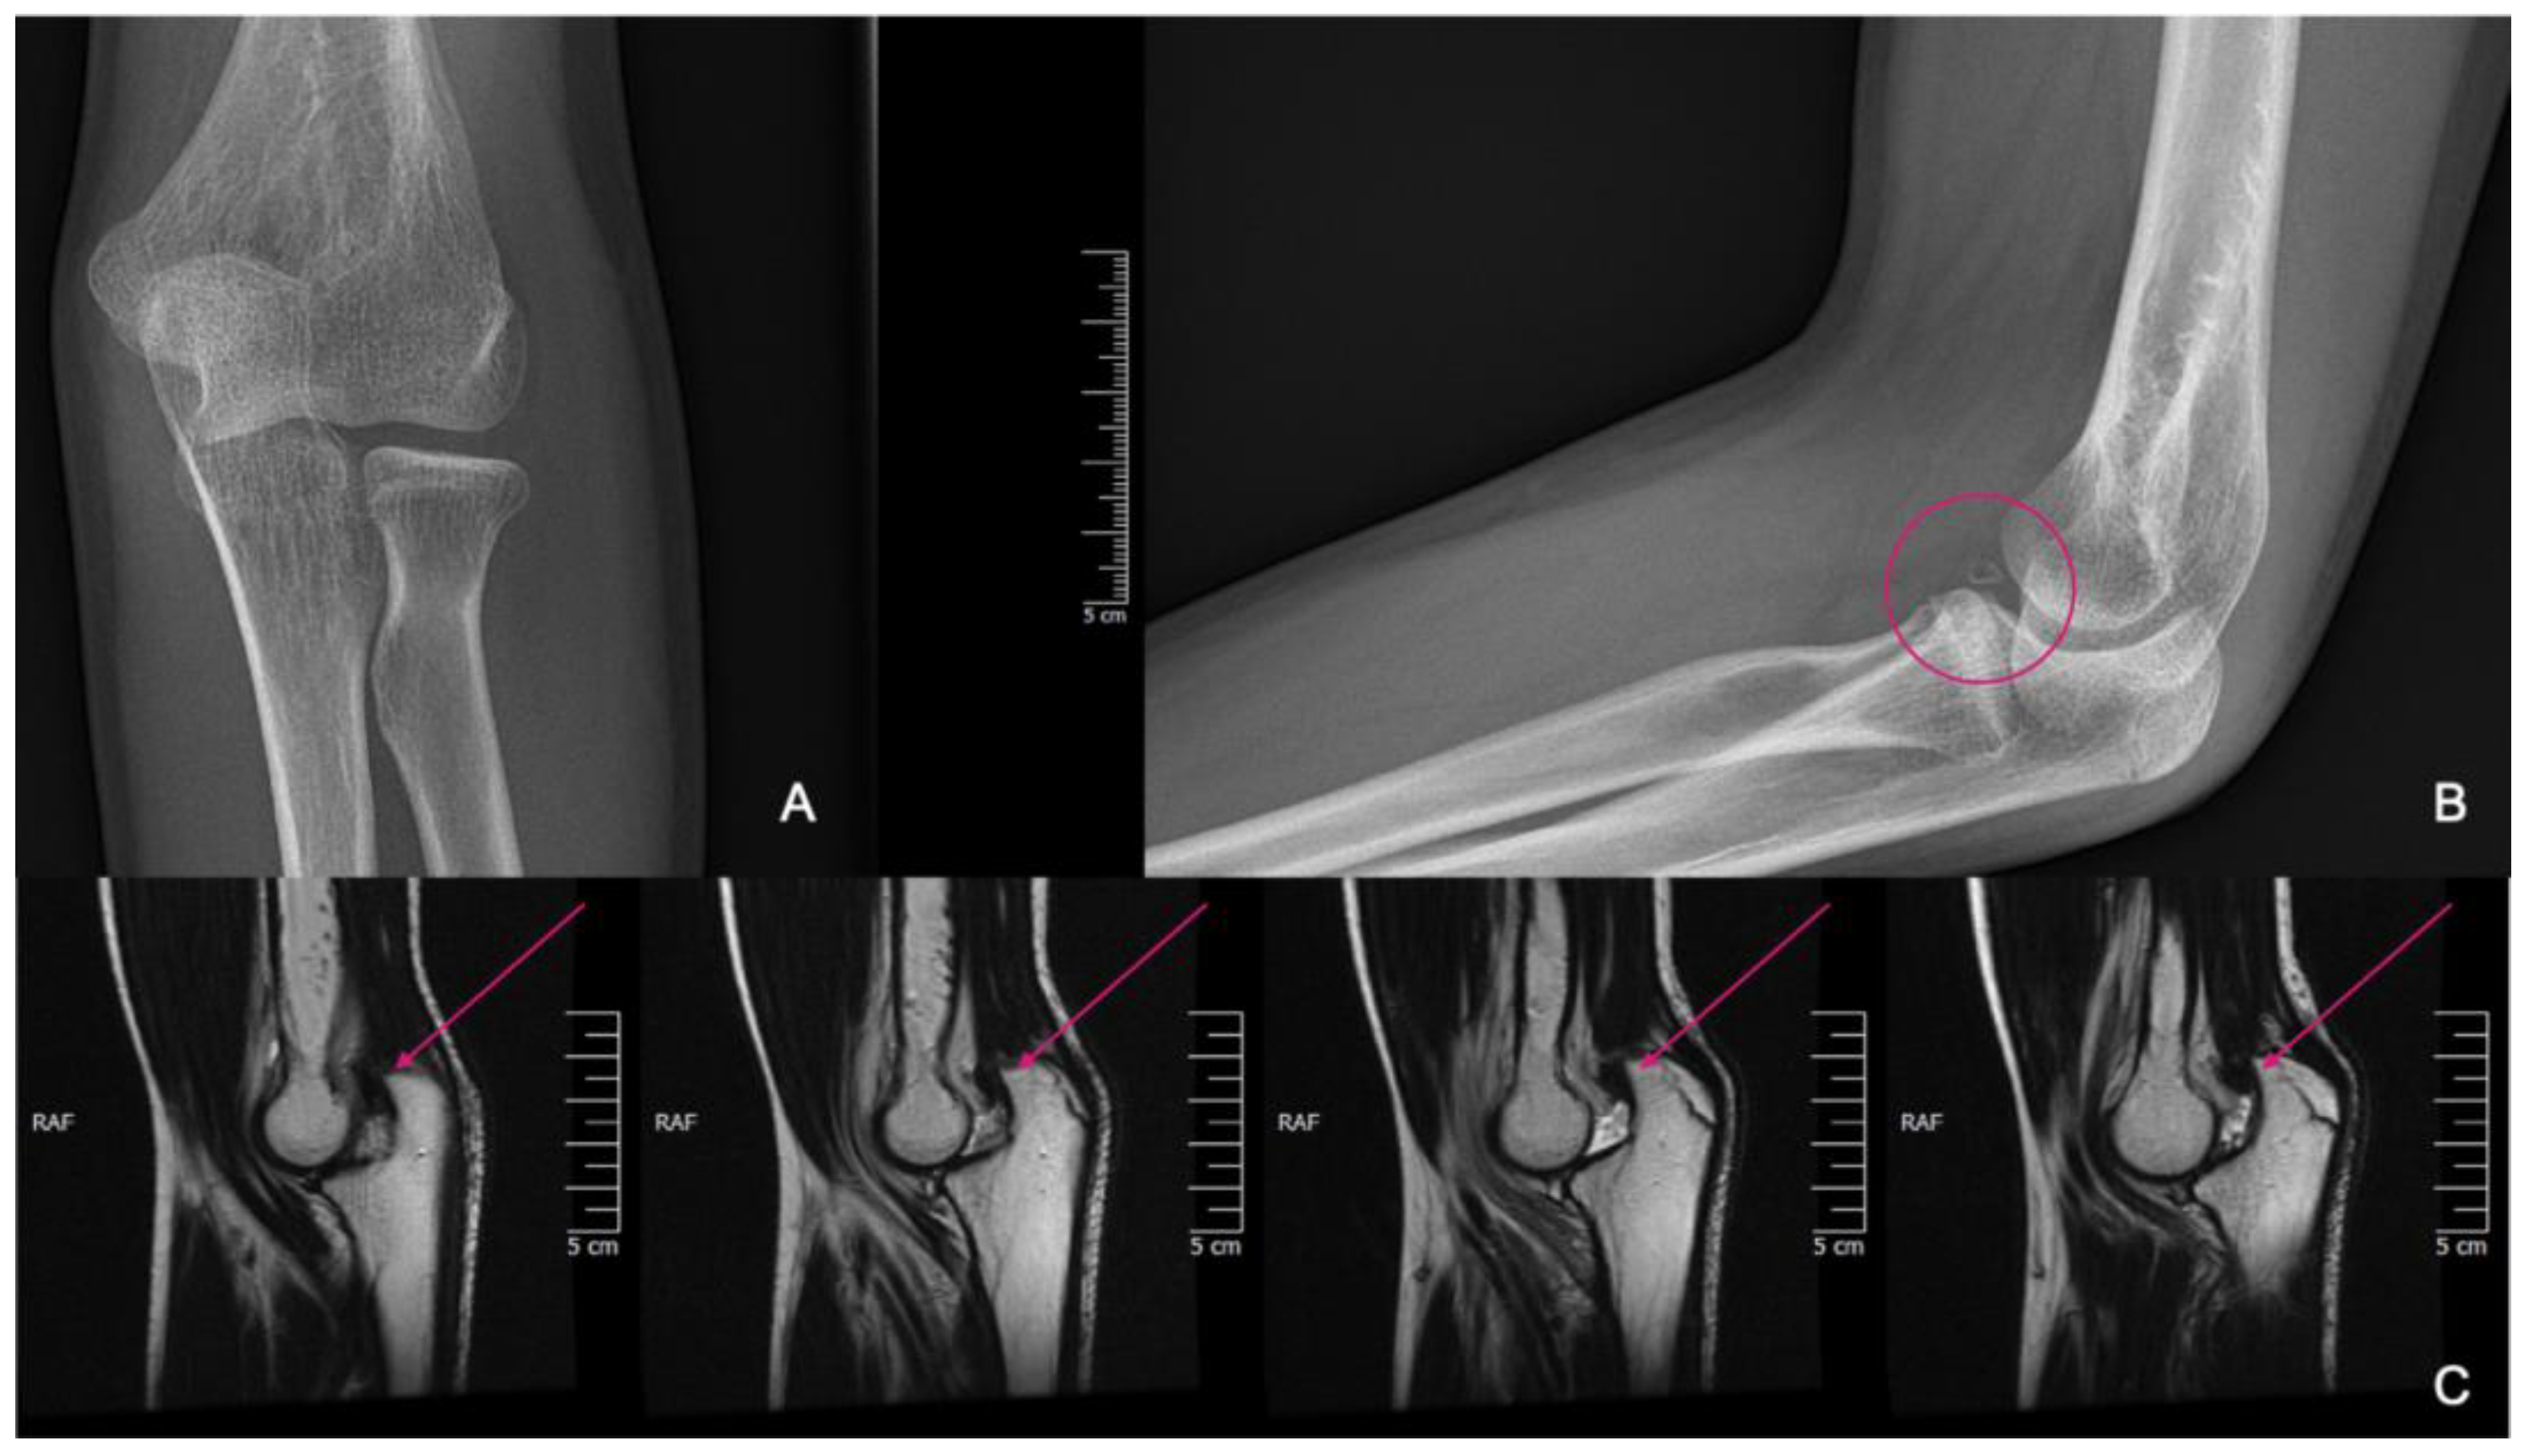

Figure 2.

CT images were provided for surgical planning; the defect can be seen highlighted in the pink circle.

Figure 6.

X-rays showing fragmentation, highlighted by the pink circle (A,B). Subluxation is visible on the MRI pointed at with pink arrows (C).